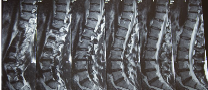

척추디스크 증상 원인 치료방법 알아보아요 척추디스크 증상 원인 치료방법 등 척추디스크 관련 정보에 대해 알아보도록 하겠습니다. 척추 디스크란 척추뼈 사이에 있는 연골 조직이 손상되거나 눌려서 신경을 자극하거나 압박하는 질환입니다. 허리 통증, 다리 저림, 근육 약화 등의 증상을 유발할 수 있습니다.

척추 디스크 치료방법에 대해 알아보겠습니다. 척추 디스크란 척추뼈 사이에 있는 연골 조직으로, 척추를 보호하고 쿠션 역할을 합니다. 하지만 나이가 들거나 외부 충격, 과도한 운동, 자세 등의 문제로 인해 디스크가 손상되거나 변형되면 허리통증이나 다리 저림, 마비 등의 증상을 유발할 수 있습니다. 이러한 디스크 질환에는 디스크 변성증, 탈출증, 내장증 등이 있습니다.